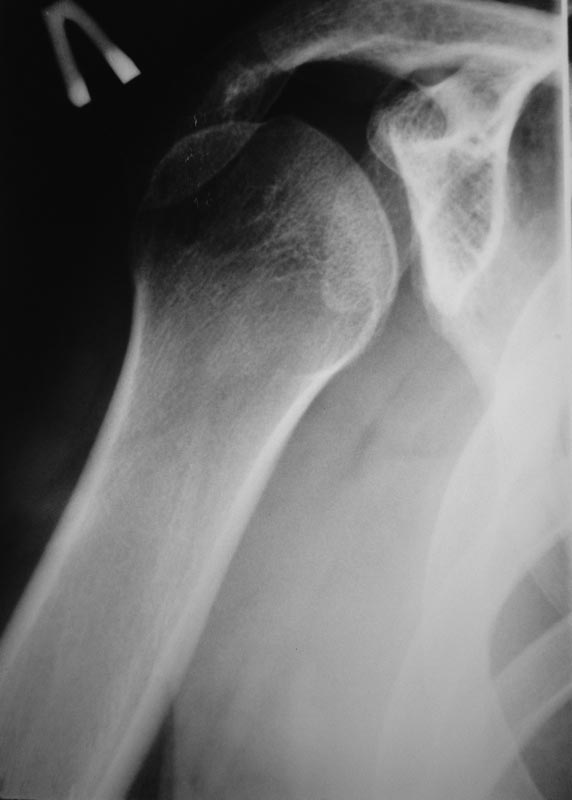

Уважаемые коллеги! Требуется ваша помощь. На консультацию обратился пациент 30 лет с

жалобами на ограничение активных движений в левом плечевом суставе.

Пассивные в полном объеме. Со слов имела место некая родовая травма. К тому же отмечается незначительный

дефицит иннервации n.radialis (снижение ╚ силы ╩ разгибателей-сгибателей в кистевом

суставе и отведения 1 пальца; неврологи никакого специфичного лечения не назначают). Также

имеется контрактура локтевого сустава: сгибание в полном объеме, разгибание 150 градусов,

супинация в пределах 7 градусов. Функция конечности в принципе устраивает. Скелетных травм

в анамнезе нет. Вопрос: есть ли смысл заниматься какими-либо реконструкциям на плечевом

суставе и как можно улучшить функцию скомпрометированных суставов? Заранее всем

благодарен